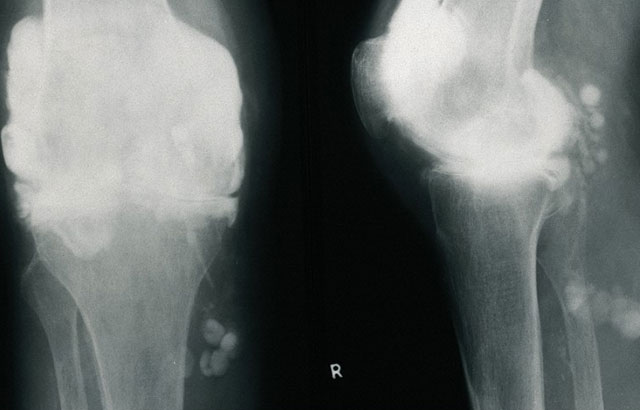

Rheumatoid arthritis of knee

Rheumatoid arthritis of the knee. Credit: Wellcome Photo Library. Wellcome Images